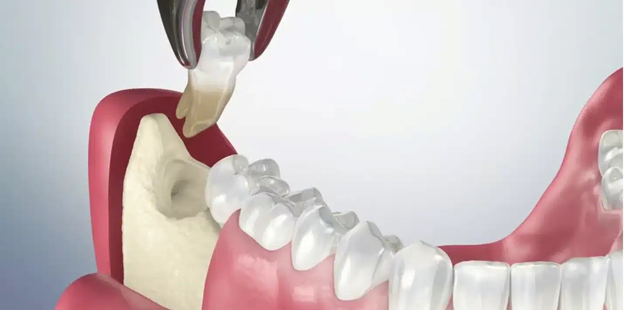

Bước 4: Nhổ răng khôn

- Răng khôn mọc thẳng, dễ: Nhổ trực tiếp, ít xâm lấn, hạn chế chảy máu, thời gian hồi phục nhanh.

- Răng mọc khó (lệch, ngầm): Chia nhỏ thân răng, tách rời từng phần để lấy ra nhẹ nhàng, bảo vệ mô mềm và xương ổ răng.

- Công nghệ hỗ trợ: Máy siêu âm Piezotome bóc tách dây chằng nha chu, giảm chảy máu và áp lực lên xương hàm.

- Kiểm soát lực nhổ: Bác sĩ giàu kinh nghiệm đảm bảo lực vừa đủ, bảo tồn xương ổ răng tối đa.

Ưu điểm: Nhổ răng khôn không đau, ít chảy máu, hạn chế xâm lấn, đặc biệt với răng ngầm hoặc lệch phức tạp.